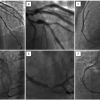

The third approach is one in which PCI is performed immediately after the surgical revascularisation, in the same session and in the same “hybrid room” [5757. Kon ZN, Brown EN, Tran R, Joshi A, Reicher B, Grant MC, Kallam S, Burris N, Connerney I, Zimrin D, Poston RS. Simultaneous hybrid coronary revascularisation reduces postoperative morbidity compared with results from conventional off-pump coronary artery bypass. J Thorac Cardiovasc Surg. 2008;135:367–375. , 5858. Gilard M, Bezon E, Cornily JC, Mansourati J, Mondine P, Barra JA, Boschat J. Same-day combined percutaneous coronary intervention and coronary artery surgery. Cardiology. 2007;108:363–367. , 6060. Reicher B, Poston RS, Mehra MR, Joshi A, Odonkor P, Kon Z, Reyes PA, Zimrin DA. Simultaneous ‘‘hybrid’’ percutaneous coronary intervention and minimally invasive surgical bypass grafting: feasibility, safety, and clinical outcomes. Am Heart J. 2008;155:661–667. ]. The availability of such a room is a ‘’sine qua non”, moreover the room itself requires not only the characteristics of an operating room and a state-of-the-art imaging equipment (including IVUS and haemodynamic monitoring capability), but also a specialised professional support for both the surgeon and the interventional cardiologist. Dual antiplatelet therapy can be given immediately before the intervention. Even though tempting conceptually, this approach remains logistically cumbersome. Figure 1 shows the example of a hybrid fractional flow reserve (FFR) guided hybrid revascularisation strategy (see figure legend).